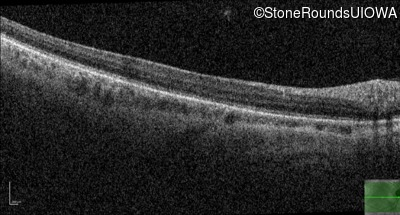

Optical Coherence Tomography - Right - 20/40

Exemplar / OCT Stack

Optical Coherence Tomography - Left - 20/25